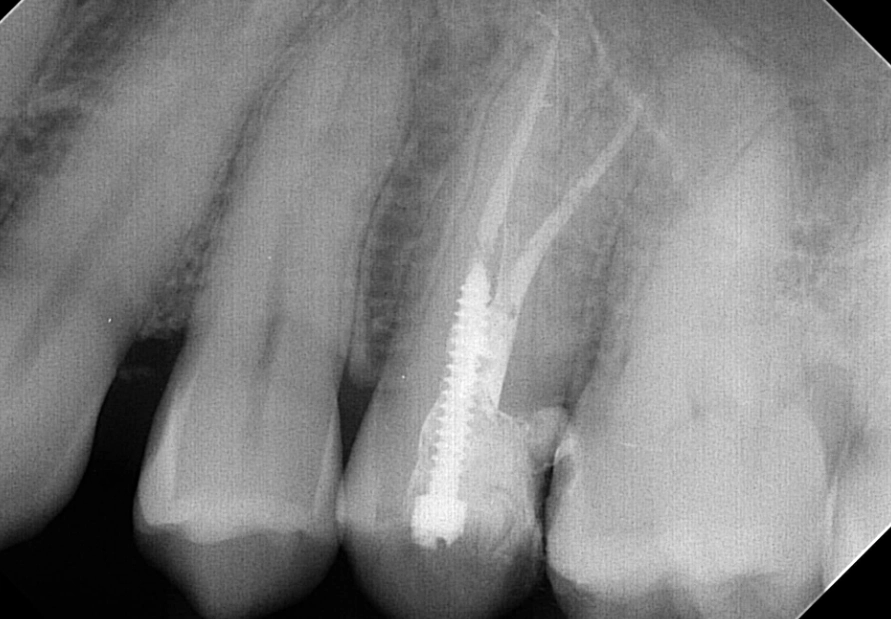

This variability is why some premolar root canals feel straightforward, while others require the precision of a specialist (an endodontist). I once had a patient whose upper first premolar had three separate canals—a configuration you won't find in any textbook but happens more than people think. If a dentist isn't using a dental microscope and only takes one standard X-ray, they might completely miss an extra canal, leaving infected tissue behind. That tooth will hurt again in six months, guaranteed.

First, good imaging is non-negotiable. A periapical X-ray shows the length of the roots. For complex cases, a 3D cone beam CT scan might be used. This gives a detailed map, crucial for navigating those tricky, multi-canal premolars. Your dentist will also administer local anesthesia. The idea that root canals are painfully done is a complete myth—if you feel sharp pain, speak up. More anesthetic can be given. You should only feel pressure.

Access and Cleaning: A small opening is made in the top of the tooth. Using very fine files, the dentist removes the diseased pulp and meticulously cleans and shapes each canal. This is where the microscope is a game-changer. It allows the clinician to see intricate details, find hidden canals, and ensure no debris is left.